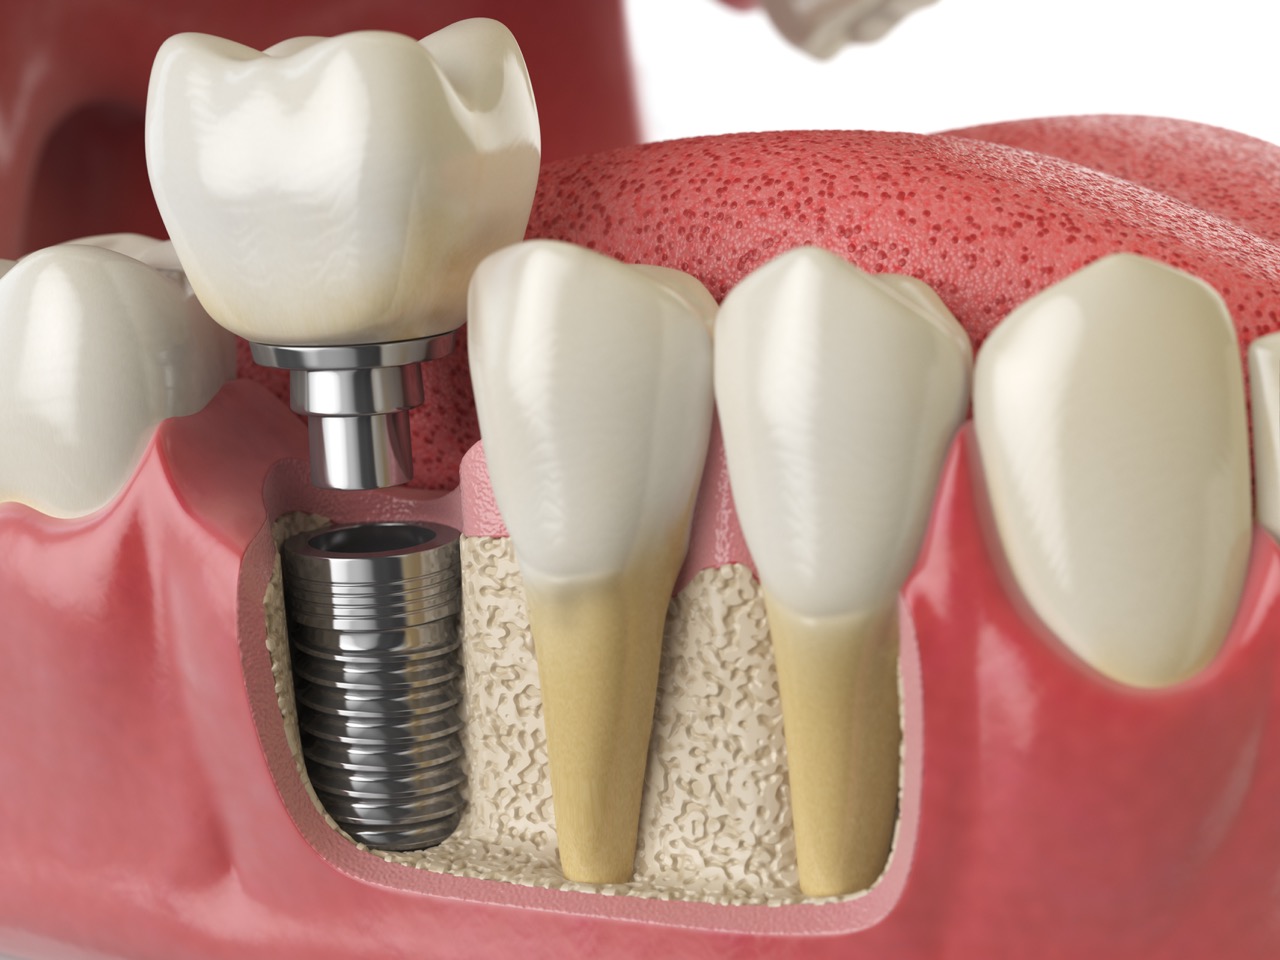

Dental Implant Restorations

If you are missing teeth, it is crucial to replace them. When teeth are missing, your teeth and mouth can shift and even cause your face to look older.  Without all your teeth, chewing and eating can destabilize your bite and cause you discomfort. Implants are a great way to replace your missing teeth, and if properly maintained, can last a lifetime!

An implant is a new tooth made of metal and porcelain that looks just like your natural tooth. It’s composed of three main parts: one part is the titanium implant body that takes the place of the missing root, and the remaining parts create the tooth-colored crown on top of the implant. With implant treatment, you can smile confidently knowing no one will ever suspect you have a replacement tooth.

In addition to tooth replacement, implants may be used to anchor dentures, especially lower dentures that tend to shift when you talk or chew. For patients with removable partial dentures, implants can replace missing teeth so you have a more natural-looking smile and stronger bite.

Anatomy of healthy teeth and tooth dental implant in dentura.